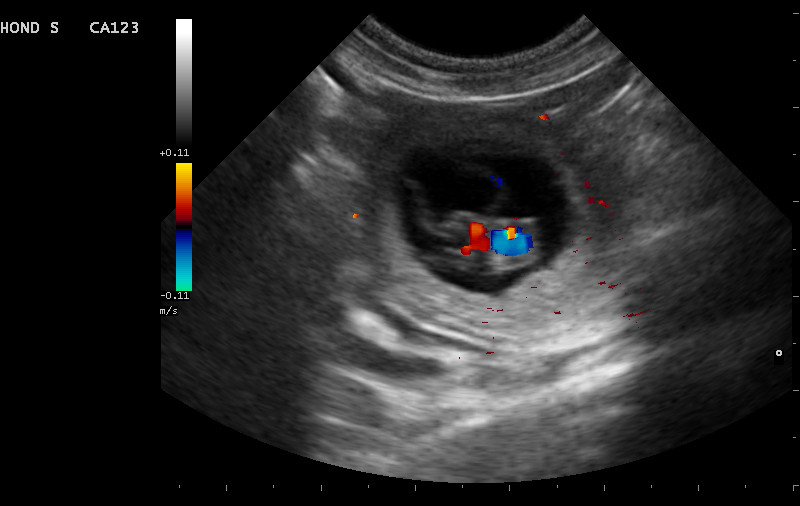

Vanaf dag 21 dagen bij de hond en 18 dagen bij de kat, is het mogelijk om te zien of een hond of kat drachtig is. Soms zijn er al eerder veranderingen waar te nemen. Het is echter betrouwbaarder om vanaf dag 28 van de dracht een echo van de baarmoeder te maken.

Er zijn dan duidelijk vruchtzakjes met foetussen zichtbaar. Vaak voeren we de echo rond dag 30 uit, omdat na die dag de kans op doodgaan en resorptie een stuk kleiner wordt.

Naast bevestigen van de dracht heeft de echo als voordeel dat het ons meer informatie geeft over de gezondheid van de pups of kittens. Er kan bekeken worden of de dracht normaal verloopt en de hartactie van de foetussen kan bekeken worden. Wanneer het moment van dekken niet bekend is, kan er een schatting gemaakt worden van de drachtduur aan de hand van het formaat van de foetussen. Hiervoor bestaan bepaalde formules, deze zijn zeker niet geheel betrouwbaar maar kunnen een richting geven. Ook kan er een schatting gemaakt worden van het aantal pups of kittens dat verwacht wordt. Het is echter belangrijk om te weten dat dit bij echo nooit met 100% zekerheid kan worden vastgesteld. Tijdens het maken van echo bewegen de foetussen, waardoor ze soms niet of juist dubbel geteld kunnen worden bij het langsgaan van de baarmoederhoorns. Ook is het zo dat hoe verder we in de dracht zitten, des te onbetrouwbaarder wordt het. Dit komt omdat de pups en kittens steeds groter worden, waardoor je meerdere keren hetzelfde pup of kitten kunt tellen.